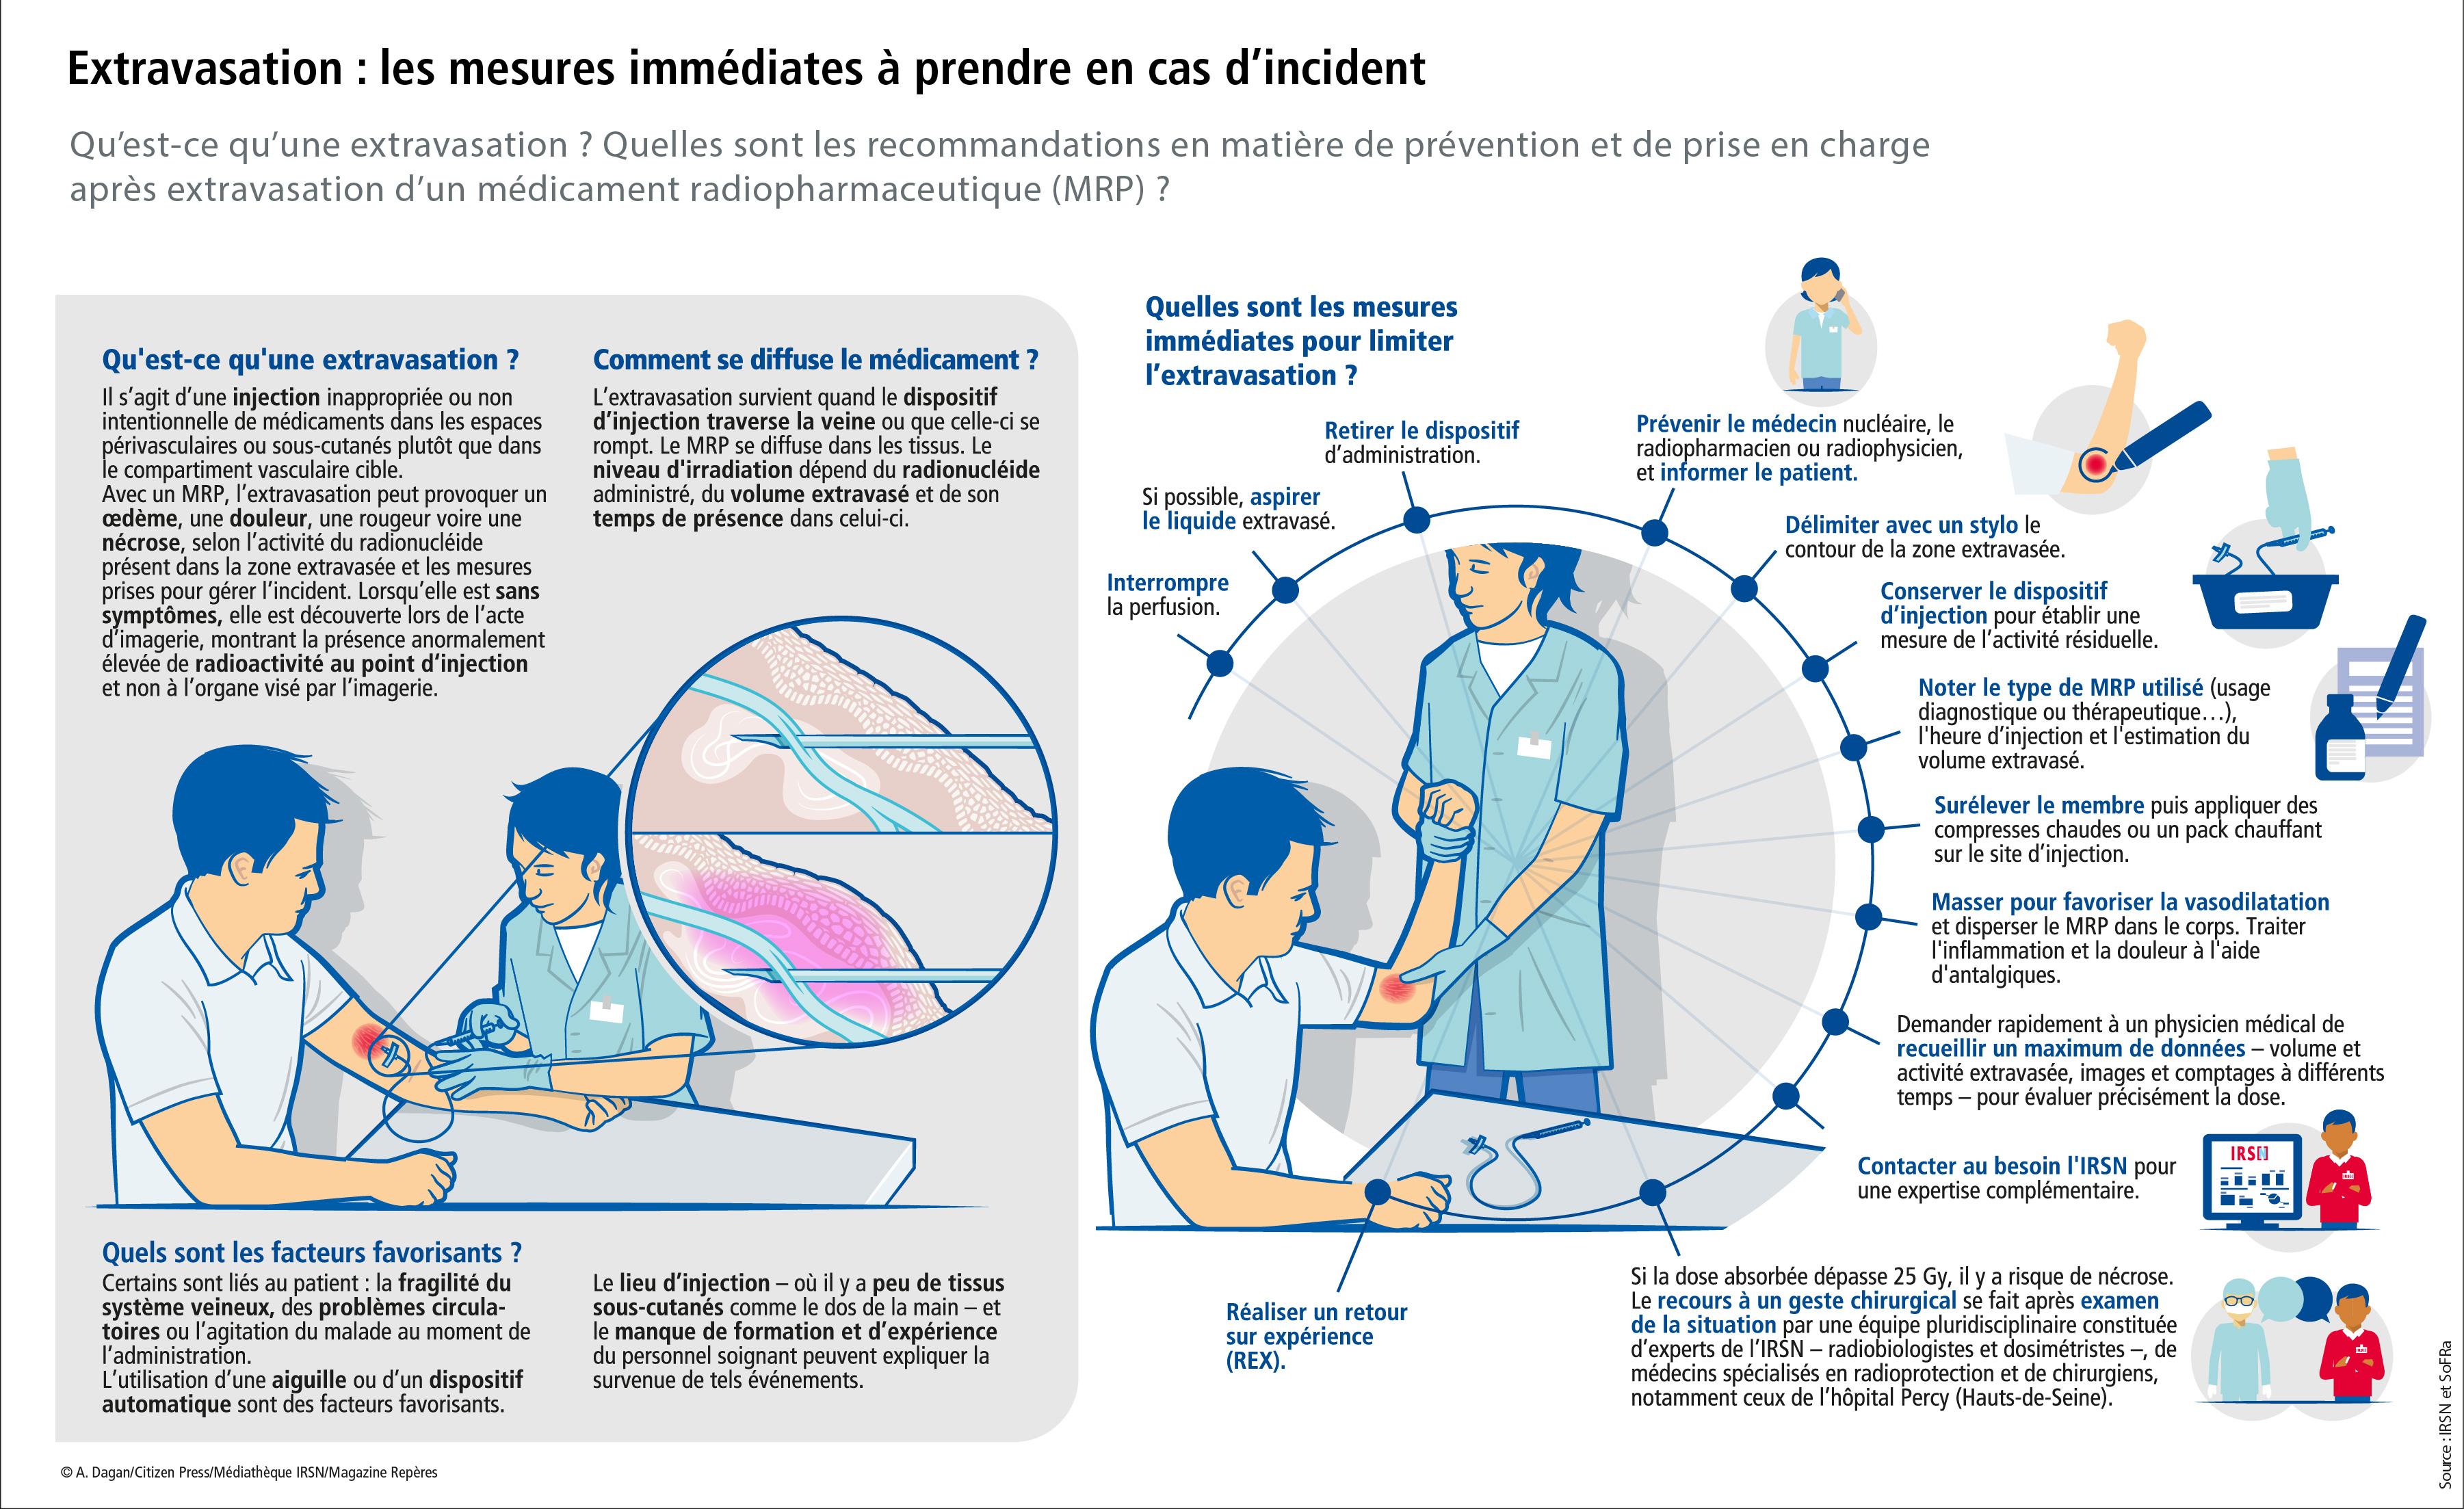

INFOGRAPHIE - Extravasation : les mesures immédiates à prendre en cas d'incident

Qu'est-ce qu'une extravasation ? Quelles sont les recommandations en matière de prévention et de prise en charge après extravasation d'un médicament radiopharmaceutique ?